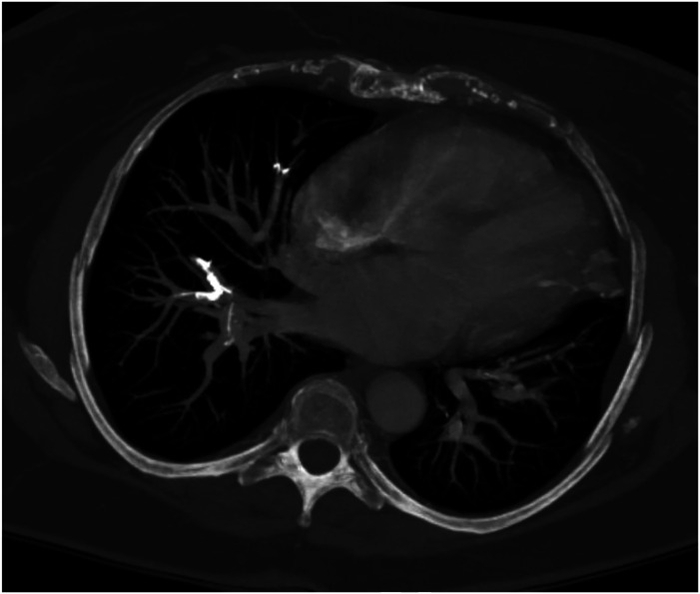

为排除转化为侵袭性淋巴瘤的可能性,对患者进行了胸、腹、盆腔的CT扫描。结果未见淋巴瘤迹象,但显示肺内存在栓塞物质。

注:计算机断层扫描显示各种肺动脉中的物质密度高于造影剂,以白色表示;血栓形成材料的密度通常低于造影剂的密度,以黑色表示。

第一位患者,在术后出现相关呼吸系统症状,由于观察到高密度以及表明肺动脉高压的右/左心室比值增加,可能是由在Th11-L3进行的椎体成形术引起的,因此怀疑骨水泥肺栓塞。